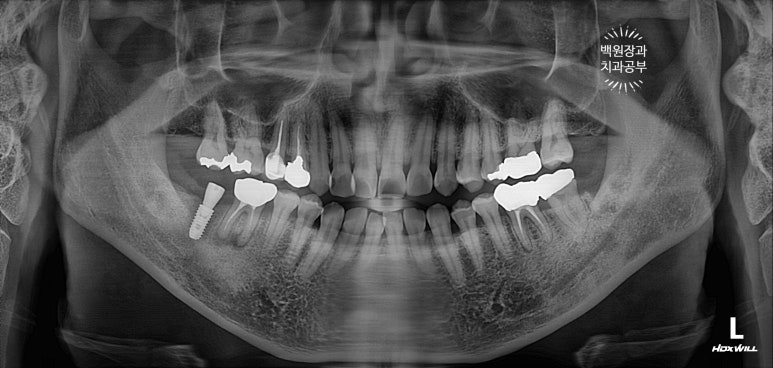

치과용 파노라마 엑스레이를 보니 오른쪽 아래 두번째 큰어금니와 왼쪽 아래 사랑니가 머리가 부러져 있네요.

그 중 오른쪽 아래 어금니는 신경치료를 하셨던 이빨인데, 이차 충치가 심해서 부러진 모양입니다.

그리하여 수술 후 치과용 파노라마 사진입니다.

임플란트 위치가 아주 듬직하니 마음에 드네요!!

임플란트 완성 후 치과용 파노라마 사진입니다.

임플란트가 이상적인 모양으로 예쁘게 제작된 것을 보실 수 있을거에요!